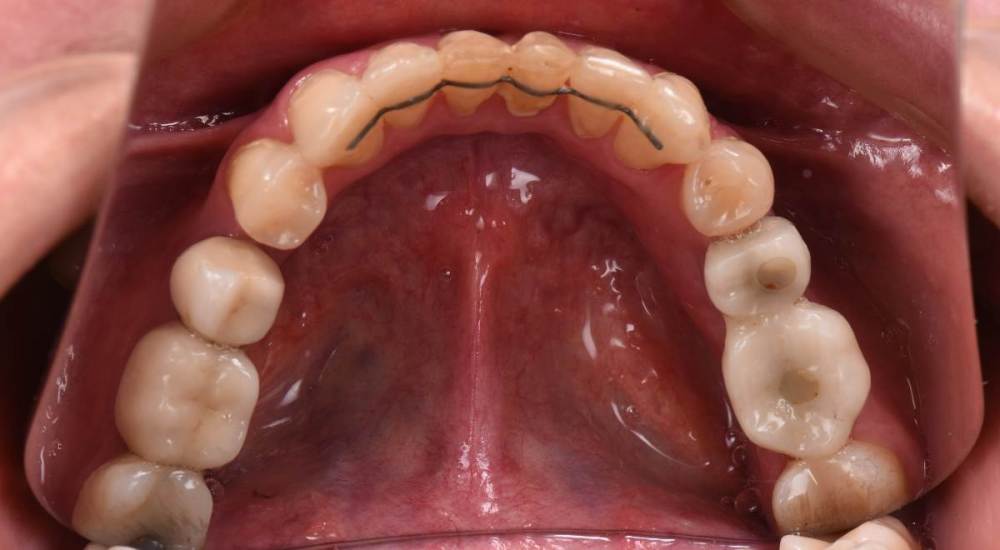

После ортодонтии и имплантации(делал не я):

21276649_.thumb.JPG.ac6bc70f88acb74ec8f69200429a4628.JPG

DSC_6448.thumb.JPG.8410ca5b1d184dbe575abfe993920475.JPG